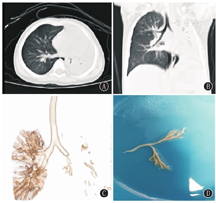

26例患儿均在随访过程中复查HRCT发现支气管扩张(图1),20例患儿HRCT同时存在"马赛克征",即PIBO,其中8例患儿存在不同程度的肺实变,5例患儿存在纤维条索影,3例患儿存在胸膜增厚,2例患儿存在肺囊泡。其中20例合并PIBO的支气管扩张患儿急性期肺实变累及范围均≥2个肺叶(20/20,100%)。24例(92.30%)为弥漫性支气管扩张(即>2个肺叶),HRCT显示支气管扩张最常累及左下叶、右下叶(各21例,80.77%),其次为右上叶(17例,65.38%),最后为右中叶、左上叶(各15例,57.69%)。20例合并PIBO的支气管扩张症患儿均为弥漫性支气管扩张。支气管扩张的类型以柱状最常见(23例,88.46%),其次为柱状-囊状并存(2例,7.69%),单纯囊状仅1例(3.85%)。

急性期住院期间,26例均因肺实变、广泛渗出而接受支气管镜检查,镜下多表现为黏膜充血、糜烂,2例并发塑型性支气管炎(图2)。15例合并PIBO的支气管扩张症患儿随访过程中因急性加重行支气管镜检查。镜下表现均为黏膜充血,管腔大量淡黄色黏稠分泌物,仅1例见"鱼骨征"(图3)。